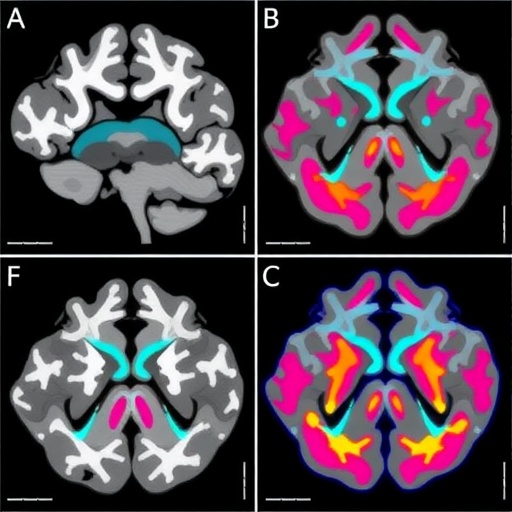

As part of the research methodology, the team utilized advanced imaging techniques such as MRI to gather comprehensive imaging profiles of the gliomas. Using this data, they extracted features that correspond to biological characteristics present within the tumors. These features were then analyzed using state-of-the-art machine learning algorithms capable of discerning patterns that may not be easily noticeable to the human eye. The initiative to harness these insights reflects an innovative approach to brain cancer research that could impact clinical practices significantly.